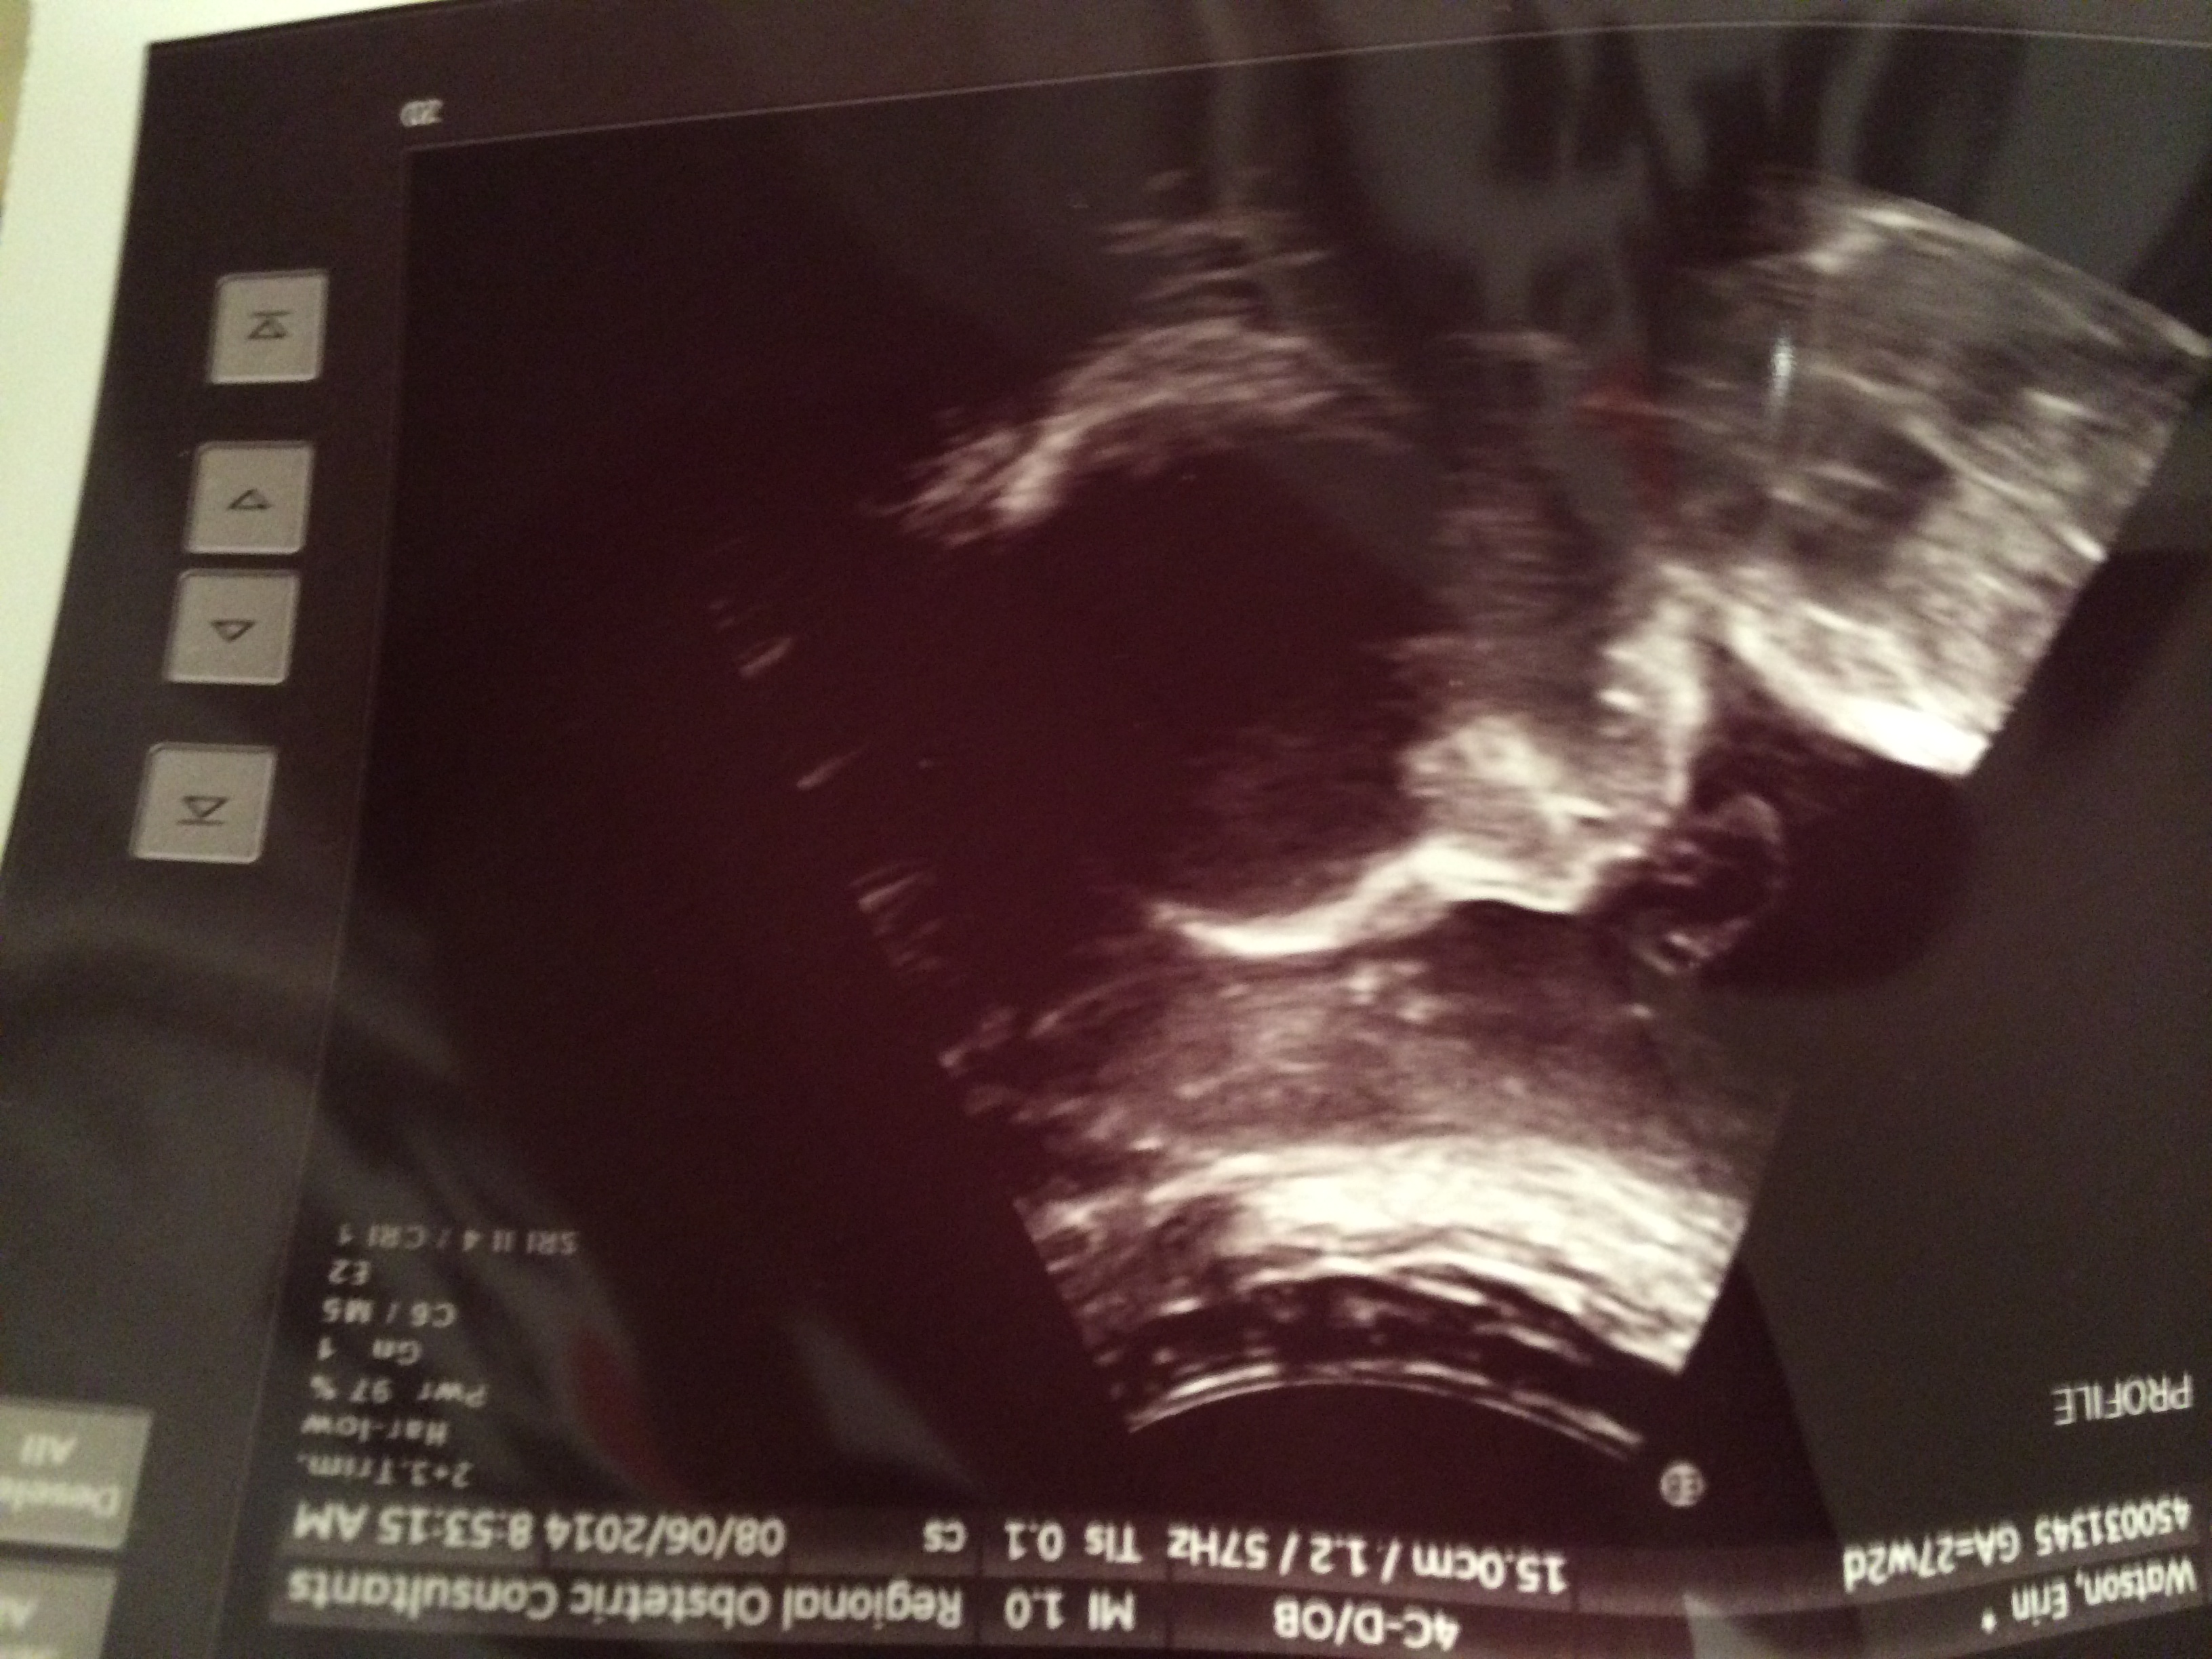

AW/Appointments: No upcoming appointments until next month. I will AW and complain. AW first. We had a follow up anatomy scan last week and it was awesome. She was moving like a little baby, smacking her lips and playing with her fingers. Oh, it just melted our hearts and got us so excited! I'm going to attach my u/s scan as well because it's the first decent one we've gotten (I have abdominal scarring that has thwarted all other attempts!)

Bad part? I got to take both a one and three hour glucose test last week and failed both. The doctor hasn't called with official results yet (but I saw the lab results online for the 3 hour) but a GD diagnosis is coming and I am not handling it super well. There were many tears. Now that I know I just want guidelines to work within and to make a plan. I feel like a bad mom for letting this happen and it's really hard on me.